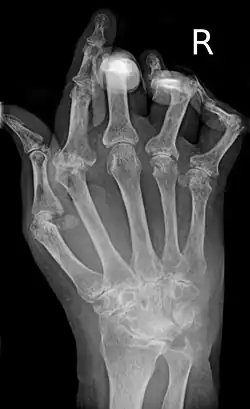

Mano afectada por la artritis reumatoide | ||

La artritis reumatoide (AR) es una enfermedad inflamatoria sistémica autoinmune, caracterizada por una inflamación persistente de las articulaciones, que típicamente afecta a las pequeñas articulaciones de manos y pies, produciendo su destrucción progresiva y generando distintos grados de deformidad e incapacidad funcional. Aunque el trastorno es de causa desconocida, la autoinmunidad juega un papel primordial en su origen, en su cronicidad y en la progresión de la enfermedad. La enfermedad se asocia con la presencia de autoanticuerpos (particularmente el factor reumatoide y los anticuerpos antipéptidos cíclicos citrulinados).[1] En ocasiones, también se presenta con manifestaciones extra articulares, pudiendo afectar a diversos órganos y sistemas, como los ojos, pulmones, corazón, piel o vasos sanguíneos.[2]

La artritis o inflamación de las articulaciones es la manifestación fundamental de la artritis reumatoide. Las articulaciones afectadas están hinchadas, calientes, dolorosas y rígidas, en especial al levantarse por la mañana o tras el reposo prolongado. Al principio pueden estar afectadas solo una o varias articulaciones, pero progresivamente se van sumando más articulaciones inflamadas —poliartritis—, siendo las que con más frecuencia se afectan las pequeñas articulaciones de las manos y los pies, aunque también es frecuente la afectación de otras articulaciones más grandes como los codos, los hombros, las rodillas o los tobillos.[49] La rigidez matinal es, con frecuencia, un dato destacado de la enfermedad y suele durar más de una hora. Estos datos ayudan a distinguir a la artritis reumatoide de otros problemas no inflamatorios de las articulaciones, como la artrosis u otros tipos de artritis. Las articulaciones se afectan habitualmente de un modo simétrico —afectando articulaciones semejantes en ambos lados del cuerpo—.[50] A medida que la enfermedad progresa, la inflamación articular causa erosiones y destrucción de las superficies articulares y daños tendinosos. Los dedos de las manos pueden sufrir diversas deformidades dependiendo de qué articulaciones y estructuras son las más lesionadas. Son deformidades típicas de la artritis reumatoide evolucionada los dedos en cuello de cisne, la deformidad en ráfaga cubital, la deformidad en boutonniere y el pulgar en Z.[49] La inflamación articular mantenida puede originar daños estructurales en las articulaciones, causando deformidad y pérdida funcional de la articulación afectada.[51][52]